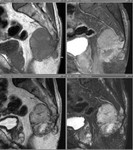

[画像診断]脊索腫について【後期研修医と学ぶ】 2011-03-31